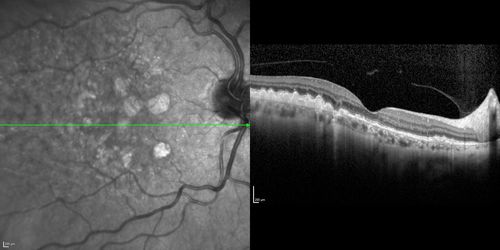

Dry AMD - Confluent Drusen Sparing Center of Macula which has Atrophy

65 year old woman, VA 20/40 OD; 20/80 OS. The center of the macula has few or no drusen with predominantly non-geographic atrophy